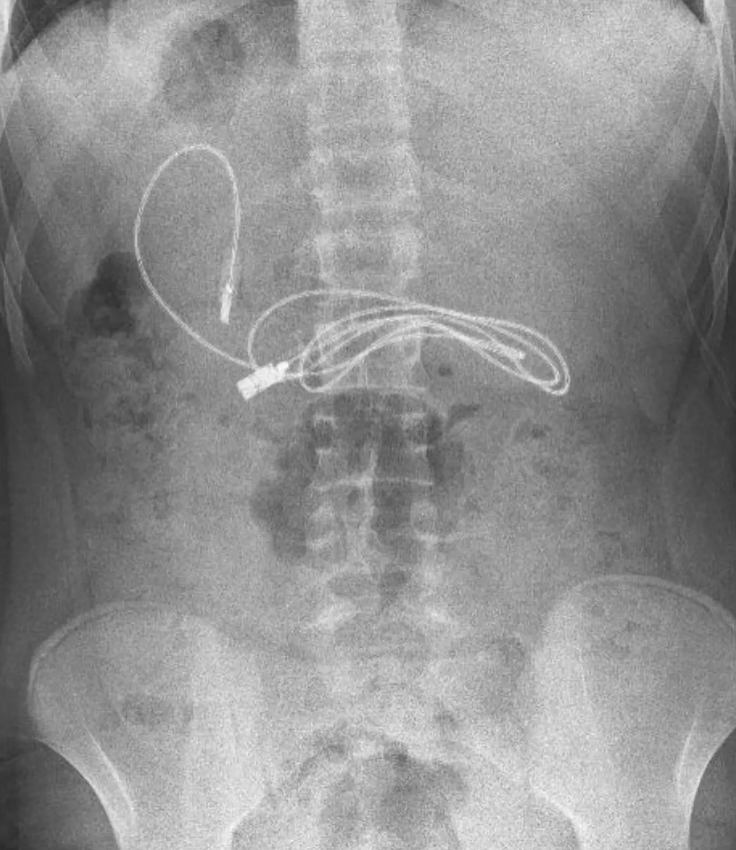

Туркийн Диарбакир хотын иргэн 15 настай хүүгийн гэр бүлийнхэн хүүгийн дотор муухайрч, гэдэс нь өвдөж байгаа гэх шинж тэмдэгтэйгээр яаралтай тусламжийн төвд иржээ. Хүүг тэр даруйд нь рентгенд харуулахад эмч нар цочирдмоор зүйл олж харжээ. Хүүгийн гэдсэнд USB кабель гацсан байсан бөгөөд нэг үзүүр нь нарийн гэдсийг нь цоолсон байв.

Эмч нар яаралтай дурангийн хагалгаа хийн 91см-ийн урттай кабель хүүгийн гэдэснээс гаргаж авсан бөгөөд энэ үеэр үсний боолт мөн гарч ирсэн байна.